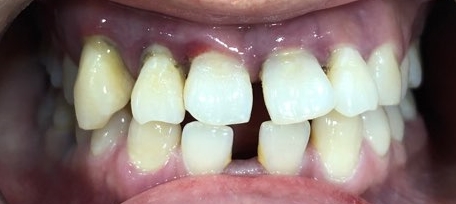

이번에는 앞니가 너무 벌어져서 보기싫던 20대 후반 남자 환자분의 변화 증례를 보여드리겠습니다.

환자분이 정보전달을 위해 공개에 동의하셨습니다! 감사합니다!

처음오셨을 때 상태이구요

앞니가 벌어져 있다보니 발음도 많이 새는 상태이구요.

아래 앞니는 일반적인 분들보다 2개가 없는 상태였구요,

위 앞니 중에 화살표 된 치아는 굉장히 많이 흔들리는 상태였습니다.